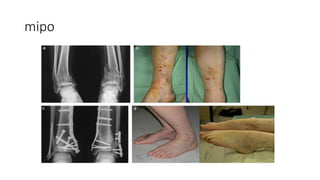

mipo

Bridge plating • Bridgeplating techniques are used for multifragmentary long bone fractures where intramedullary nailing or conventional plate fixation is not suitable. • The plate provides relative stability by fixation of the two main fragments, achieving correct length, alignment, and rotation. The fracture site is left undisturbed and fracture healing by callus formation is promoted. • To leave the fracture site as undisturbed as possible, bridge plates are often inserted through a minimally invasive approach.